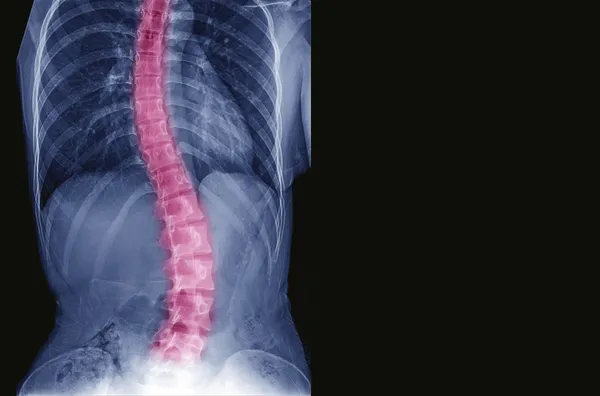

Skolyoz yani omur eğriliği birçok insanda rastlanabilen bir rahatsızlıktır. Normal bir insanda yer alan omurganın biçimsiz şekildi sağa veya sola doğru eğri durmasından kaynaklanmaktadır. Özellikle 30 dereceyi geçen skolyozlar genç kızlarda erkeklere oranla on kat fazla görülmektedir. Peki, Skolyoz belirtileri nelerdir? Omur eğriliği ameliyatı kaç yaşına kadar yapılır? İşte detaylar…

Omurgadaki bir eğri vücudun sola veya sağa eğilmesine neden olabilir. Skolyozunuz varsa, bir tarafa yaslanmış gibi görünebilirsiniz. Bazı insanlar diğerlerinden daha yüksek bir omuza veya diğerinden daha fazla çıkan bir omuz bıçağına sahiptir. Omurganız bükülmüşse, göğüs kafenizin bir tarafı büküldüğünüzde daha fazla sıkışabilir.Genellikle, skolyoz belirgin değildir. Bu nedenle sağlık hizmeti sunanlar düzenli muayenenizin bir parçası olarak bir skolyoz muayenesi yapar. Bazı ülkelerde okula dayalı skolyoz tarama programları vardır.

Skolyozlu kişilerin omurgasında "S" veya "C" gibi görünebilecek yan yana bir eğri vardır.

Skolyoz, omurun düz olmak yerine eğri bir çizgi oluşturmasıdır. Küçük eğriler genellikle sorunlara neden olmaz. Ancak daha da kötüye giden bir eğri, bir kişinin sağlığı için kötü olabilir. Çok büyük eğriler eklemlere zarar verebilir ve omurganın artritine neden olabilir. Büyük eğriler, kaburgaların sürtünmesine ve ağrıya neden olabilir. Omurga çok fazla kıvrılırsa, insanlar akciğer problemleri yaşayabilir.